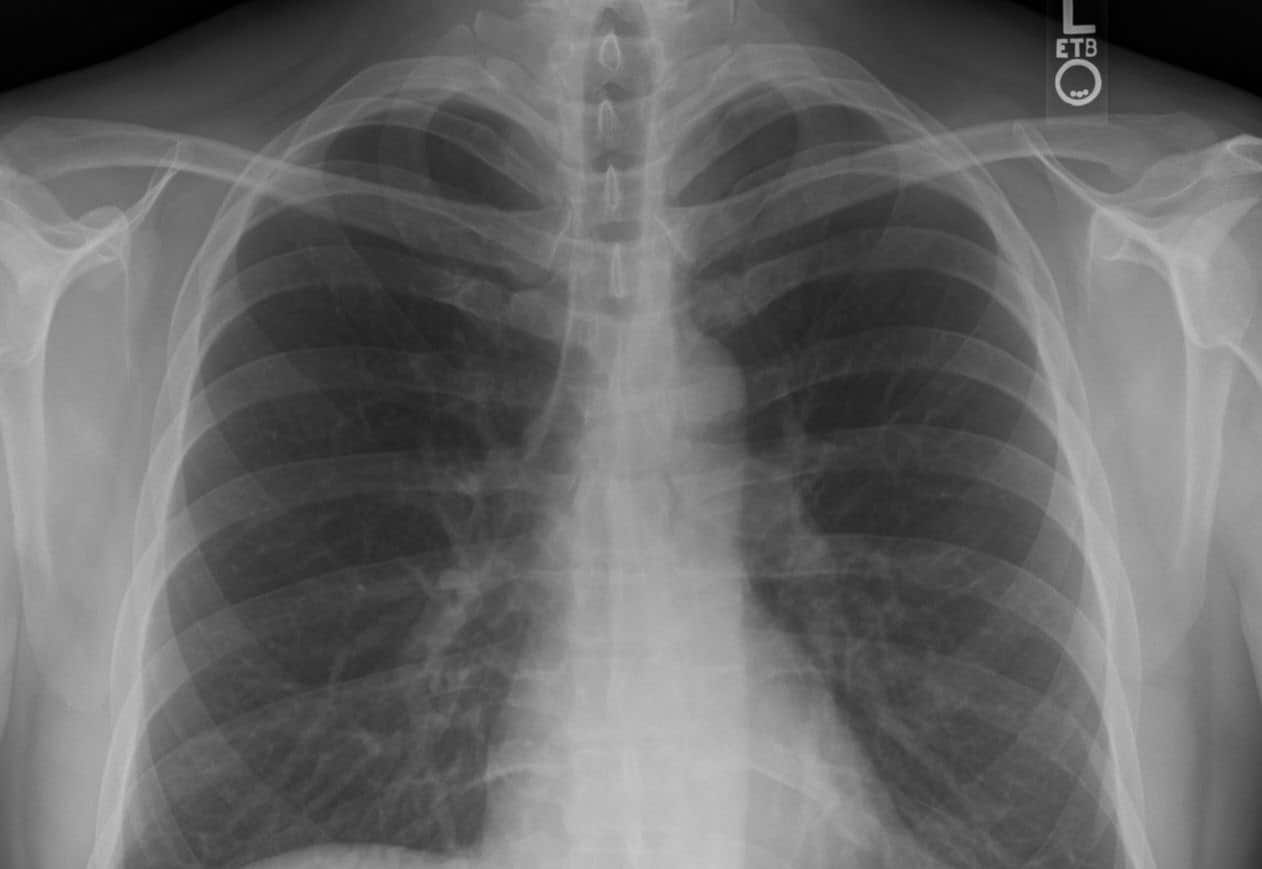

Рентгенограмма грудной клетки в прямой проекции / © Stillwaterising, Wikipedia